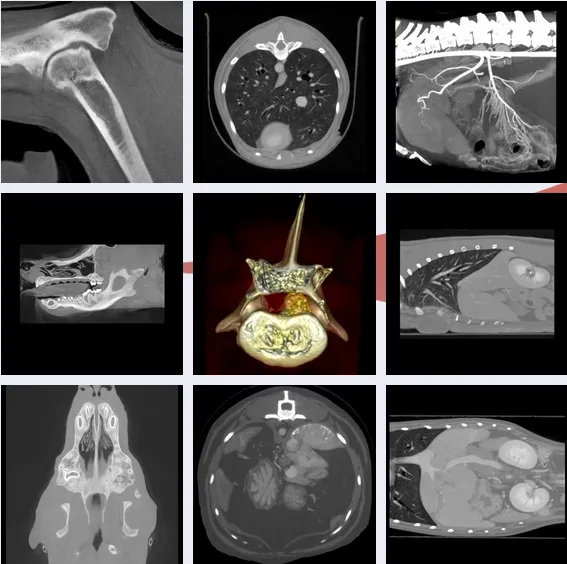

Gulf Shore Veterinary Specialty Surgery offer Computed Tomography (CT) Scans

Advanced imaging is often an important aspect of your pet's diagnosis and surgical planning.

CT studies